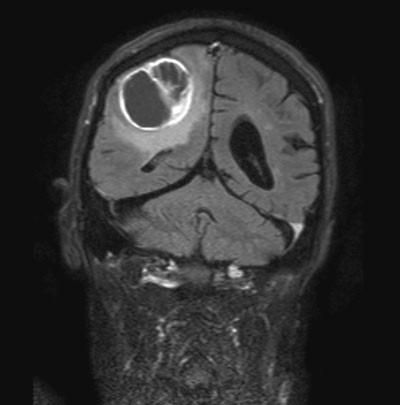

Ett år senere utviklet han i løpet av få uker økt rigiditet i armer og ben. Han hadde behov for hjelp til av- og påkledning og fikk derfor plass på sykehjem. Ved oppfølgende klinisk nevrologisk undersøkelse ble det avdekket markert rigiditet både aksialt og i armer og bein. Han hadde vansker med å reise seg fra en stol, og gikk svært langsomt og ustøtt. Det ble ikke påvist unormale reflekser eller spastisitet ved undersøkelsen. Tilstanden ble tolket som økende parkinsonisme, og levodopadosen ble derfor økt til 400 mg per døgn. Han ble imidlertid verre på tross av doseøkningen, og tre uker senere ble han innlagt ved nevrologisk avdeling. Personalet ved sykehjemmet rapporterte at han de siste to ukene før innleggelsen var blitt ute av stand til å gå. Pasientens fastlege hadde i mellomtiden økt levodopadosen til 600 mg per døgn uten bedring. Ved innkomst var han trett, men åpnet øynene på tiltale. Han var orientert for tid og sted. Kraftundersøkelse var vanskelig å utføre, men han klarte ikke å sitte uten støtte. Refleksene og sensibilitetsundersøkelser var normale. Det ble ikke påvist tegn til spastisitet eller unormale reflekser på innleggelsestidspunktet eller ved oppfølgende kliniske undersøkelser under oppholdet. MR av hjernen viste en kontrastladende tumor på 4 x 6 x 4 cm i høyre parietalregion (fig 1). Han ble operert, og histopatologisk undersøkelse viste glioblastoma multiforme. Pasienten døde få uker senere.

Glioblastoma multiforme er en høygradig infiltrerende hjernesvulst som har en median overlevelse på ca. ett år. Svulsten kan vokse raskt, og er vanskelig å behandle. Det er derfor ikke overraskende at denne ikke ble påvist ved MR-undersøkelsen som ble utført pga. synsproblemer året før svulsten ble oppdaget.